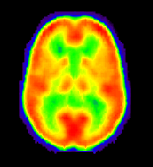

Thisfigureshows

the evolution of image quality from the first PET scanner, available in

1975, to the latest and most sophisticated model, ECAT Exact HR+. You can

easily see how the finer detais of internal brain structures can be visualized

much better in the latest model. This improvement has been achieved with

a larger number and better radiation sensors, better computer programs

and the possibility of getting several slices at the same time (using many

rings of sensors). All models of PET machines depicted here were produced

by the Siemens biomedical equipment manufacturer, which has installed the

majority of PET scanners in the world.